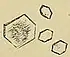

60% | when urine is acidic (decreased pH)[71] | Black/dark brown ![]() |

Calcium oxalate crystals can come in two varieties. Calcium oxalate monohydrate can appear as 'dumbbells' or as long ovals that resemble the individual posts in a picket fence. Calcium oxalate dihydrate have a tetragonal "envelope" appearance.[75]

Uric acid stones appear as pleomorphic crystals, usually diamond-shaped. They may also look like squares or rods which are polarizable.[75]